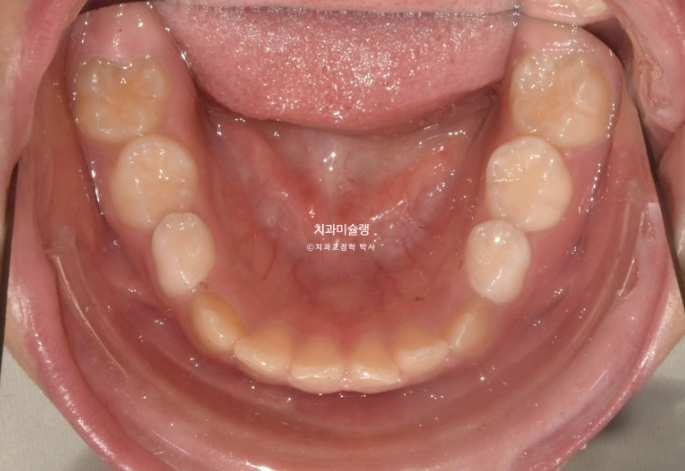

그 사이 남아있던 유치들은 모두 빠지고 이제는 완전한 영구치열로 접어들었습니다.

중심선이 여전히 틀어져 있는 이유는

파란 화살표의 잔존유치가 정상영구치보다 사이즈가 1.5배 크기 때문입니다.

하지만 어금니 교합은 1급 교합관계를 달성했고

파란 화살표 잔존유치는 초진에 비하여 치근흡수 없이 잘 보존되었습니다.

다른 영구치들에 치근흡수는 없고 치근평행도는 좋습니다.